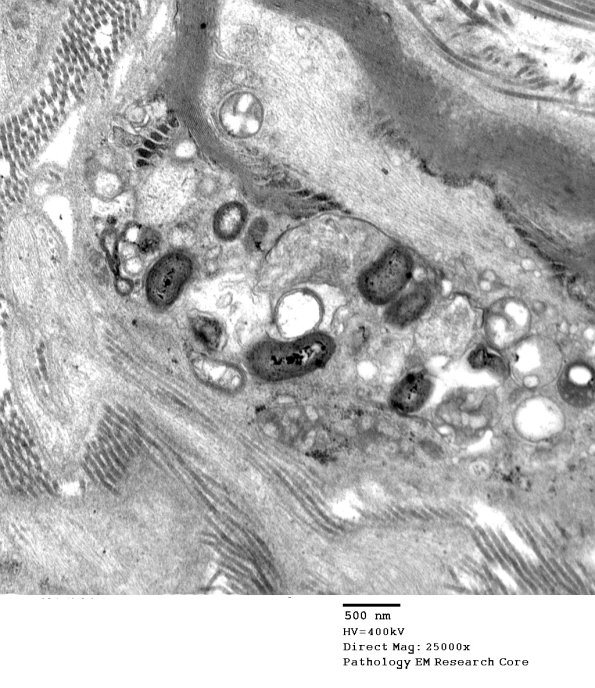

A macrophage with myelin debris is intimately associated with a paranodal axon. (electron micrograph)